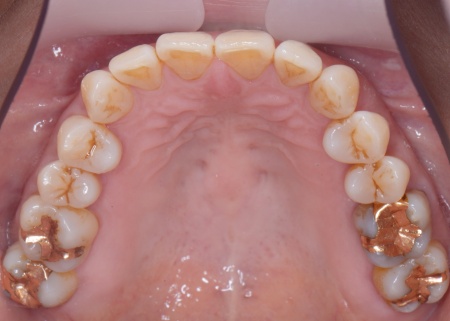

60代女性 重度の歯周病に対して歯周組織再生療法とインプラント治療を施した例

拝見したところ、上下左右の奥歯計8本(第1大臼歯、第2大臼歯)に重度の歯周病が認められました。

上左右の奥歯についても歯周組織再生療法を行い、歯をできるだけ残せるよう治療を進めました。

また、左上の奥歯は虫歯を取り除いたあと、歯の形を整えて型取りを行い、最終的にジルコニアクラウンを装着しています。

段階的に治療を進め、すべての治療を終了しました。